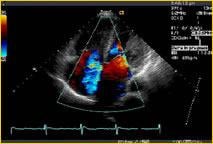

Digisonics’ DigiView cardiovascular solutions aim to bring together high-performance image analysis, professional reporting, an integrated clinical database and a PACS image archive all into one system.